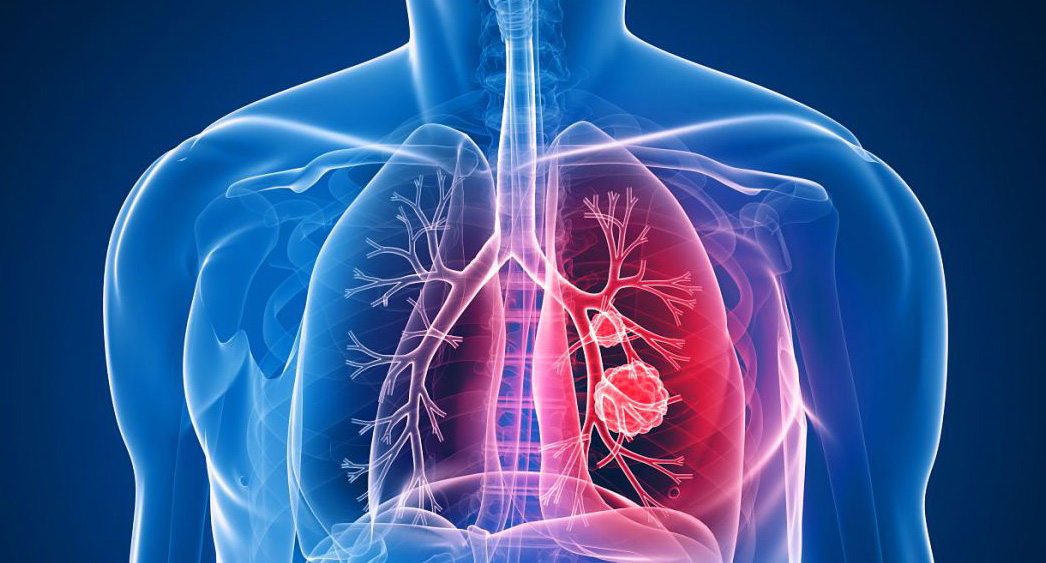

폐암의 초기증상 중에 흉통이 있습니다. 폐암 환자의 약 1/3이 흉통을 호소합니다. 흉통의 원인은 폐 가장자리에 종양이 형성되어 암세포를 생성하고 흉벽과 흉막에 침착되어 통증을 유발하는 것입니다.

흉통의 원인은 여러 가지가 있을 수 있지만, 오늘날 우리가 다루고 있는 폐암으로 인한 흉통은 경미한 통증보다는 지속적인 따끔거림과 둔한 통증을 동반한다는 점에 유의하시기 바랍니다. 또한 암은 흉막이나 흉벽 대신 갈비뼈로 퍼져 통증을 유발할 수 있습니다. 종양은 주변 조직 세포를 자극할 수 있으므로 계속해서 통증을 유발하는 경우 의사의 진찰을 받는 것이 좋습니다.